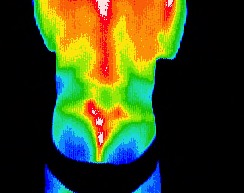

L gluteal pain (Swimmer's nemesis)